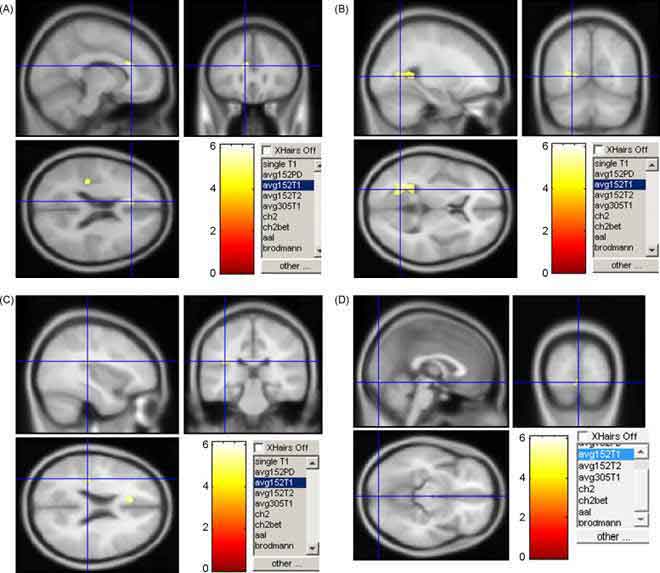

Come previsto, dopo l’assunzione della psilocibina si osservano profondi cambiamenti nello stato di coscienza. I dati ottenuti con le tecniche di fMRI, d’altra parte, hanno fornito risultati significativi e tra loro coerenti: la psilocibina induce una significativa diminuzione del flusso sanguigno e dell’ossigenazione venosa sia nelle strutture subcorticali sia in quelle corticali. Sorprendentemente, la massima diminuzione nel flusso sanguigno nel cervello e del segnale BOLD è stata osservata nelle regioni del talamo e delle porzioni anteriore e posteriore della corteccia cingolata (ACC e PCC), considerati due snodi centrali nella struttura delle connessioni presenti nel cervello umano. Inoltre, la sostanza sembra interrompere l’accoppiamento funzionale tra la PCC e la corteccia prefrontale mediale.

Queste evidenze strumentali rafforzano l’ipotesi che gli effetti soggettivi delle droghe psichedeliche siano causati da attività e connettività diminuite rispetto al normale nei centri di comunicazione fondamentali del cervello, lasciando spazio all’emergere di contenuti cognitivi scollegati tra loro. Infine, i ricercatori sottolineano che, malgrado in genere si presuma che le sostanze psichedeliche agiscano incrementando l’attività neurale, i loro risultati mettono in forse questa convinzione.